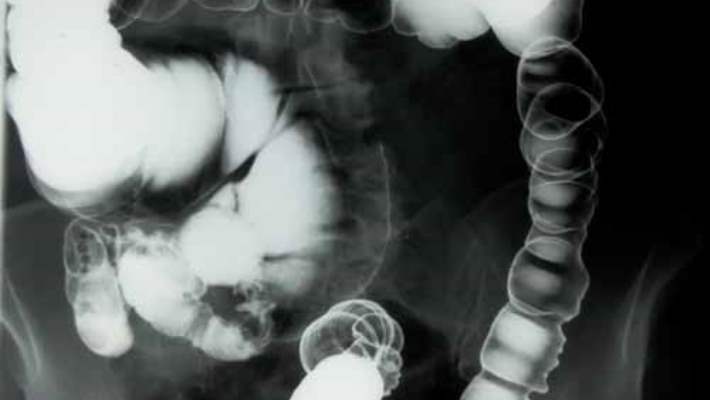

Kolonoskopi, kalın bağırsaktaki (kolon) ve rektumdaki anormallikleri veya değişiklikleri saptamak için kullanılan bir muayenedir. Kolonoskopi genel anlamda kolon kanseri taraması için altın standart olarak görülür.

Muayene, muayene masasına genellikle yan ve dizlerinizi göğsünüze doğru çekmiş vaziyette yatmanızla başlar. Doktorunuz kolonoskopu rektumunuzdan içeri sokar. Bütün kolonunuza ulaşabilecek kadar uzun olan skopun, bir fiber optik ışığıyla doktorunuzun kolonunuzun içine hava pompalamasını sağlayan bir kanalı olur. Hava kolonu şişirir, bu da kolonun iç çeperinin görünümünün iyileştirmesini sağlar. Skop hareket ederken ya da hava verilirken karın krampı ya da bağırsak hareketi isteği hissedebilirsiniz.

Kolonoskopun ucunda ince bir kamera da bulunur. Kamera, dışarıdaki bir monitöre görüntüleri aktarır ve böylece doktorunuz kolonunuzun içinde çalışabilir. Ayrıca doktorunuz doku örneği almak veya polipleri ya da diğer anormal doku alanlarını çıkarabilmek için kanalın içinden cerrahi aletleri sokabilir.

Doktorunuz skop aracılığıyla edinilen görüntülerin kalitesinden memnun değilse, kolonoskopinin tekrar edilmesini ya da bir sonraki kolonoskopinin daha kısa sürede gerçekleştirilmesini önerebilir. Eğer doktorunuz skopu tüm kolonunuz boyunca ilerletemediyse, kolonunuzun kalanını inceleyebilmek için baryumlu lavman ya da virtüel kolonoskopi önerebilir.